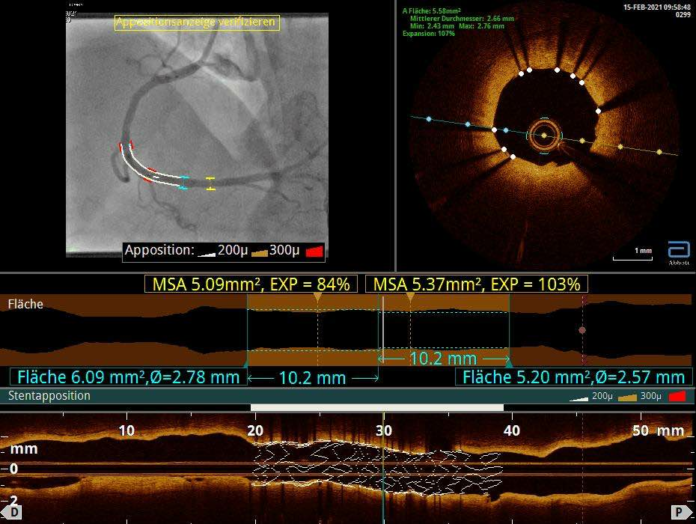

SIEGEN. Die koronare Herzkrankheit, kurz KHK, und ihre schwerwiegendste Verlaufsform, der Herzinfarkt, sind in Westeuropa die häufigste Todesursache. Bei der KHK handelt es sich um eine Verengung der Herzkranzgefäße, also der Arterien, die die Herzmuskulatur mit Blut versorgen. Kritisch verengte Gefäßstellen können mittels Herzkatheter mit einem Ballon aufgedehnt und dann mit einem Stent offengehalten werden. Aber nicht jede Intervention ist gleich: Bei manchen Patienten sind die Engstellen sehr ausgedehnt oder anatomisch erschwert zugänglich. In diesen Fällen ist besonderes Können des Kardiologen gefragt. Man spricht von einer komplexen Koronarintervention.

Zu den komplizierteren Eingriffen gehört es, wenn alle drei Herzkranzgefäße von Engstellen betroffen sind oder wenn mehr als drei Läsionen in einem Eingriff behandelt bzw. mehr als drei Stents implantiert werden müssen. Neben hoher Konzentration bei dieser Intervention, die deutlich länger dauert als ein Standardeingriff, muss der Kardiologe die einzelnen Interventionen zu einem bestmöglichen und sinnvollen Gesamtergebnis bringen. Aufwendig sind auch Eingriffe an Bifurkationen, also wenn sich ein Gefäß in zwei Äste aufspaltet. Hier müssen zwei Stents in engsten räumlichen Verhältnissen so exakt platziert werden, dass beide Gefäßäste optimal eröffnet werden. Auch die Einlage eines Stents am Hauptstamm zählt zu den komplexen Interventionen. Denn am Hauptstamm hängen gleich zwei der drei Herzkranzgefäße, was ihn zu einer der wichtigsten Stellen im Koronarsystem macht.